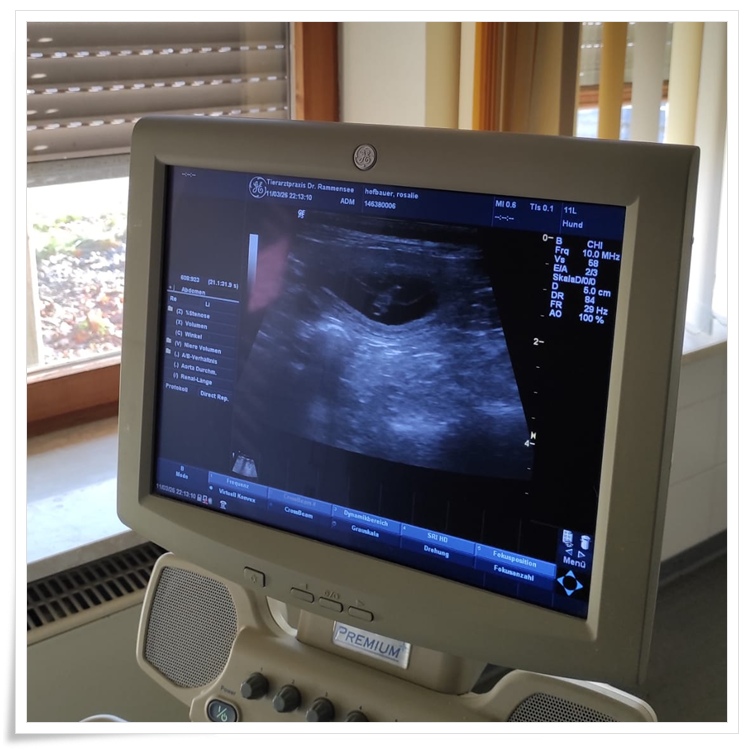

Rosalie geht es prima und wir freuen uns schon so sehr auf die kleine Wuselbande, die da im Bäuchlein wächst.

Und das Bäuchlein ist wirklich richtig gewachsen !!!

Und mit dem Stethoskop kann man schon die kleinen Herzchen tuckern hören wie ein kleines Uhrwerk.